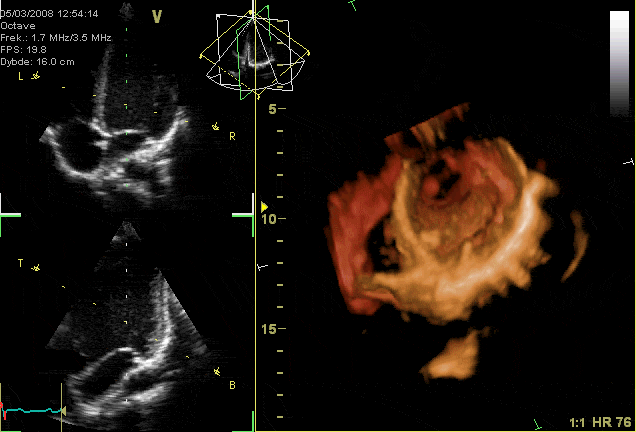

GIF-animation showing a moving echocardiogram; a 3D-loop of a heart viewed from the apex, with the apical part of the ventricles removed and the mitral valve clearly visible. Source: Wikipedia

In the microgravity environment of space, the heart no longer works against gravity, leading to reduced cardiac output and altered blood distribution. This can cause orthostatic intolerance—dizziness or fainting upon re-entry to Earth’s gravity. Studies have shown that astronauts experience a decrease in stroke volume and cardiac output during spaceflight, which can persist postflight, contributing to orthostatic intolerance. (pmc.ncbi.nlm.nih.gov) To mitigate these effects, astronauts engage in regular cardiovascular exercise and may use countermeasures like lower body negative pressure devices to maintain cardiovascular health. (pubmed.ncbi.nlm.nih.gov)